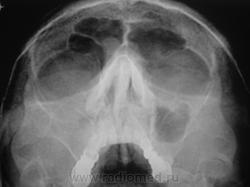

Пациент первый.

Киста, или что другое?

Больше похоже на кисту. Четкий округлый контур с характерным месторасположением. Хотя может и не так все просто)

да,  похоже на кисту, но справа снижена пневматизация верхнечел.пазухи за счет умеренного отека, я бы кисту слева под вопросом написала и направила на контроль

---------------------------------------------------------------------------------------------------------------------------------------------------------------------------------+1: как вариант,  можно предположить, что киста одонтогенного происхождения.